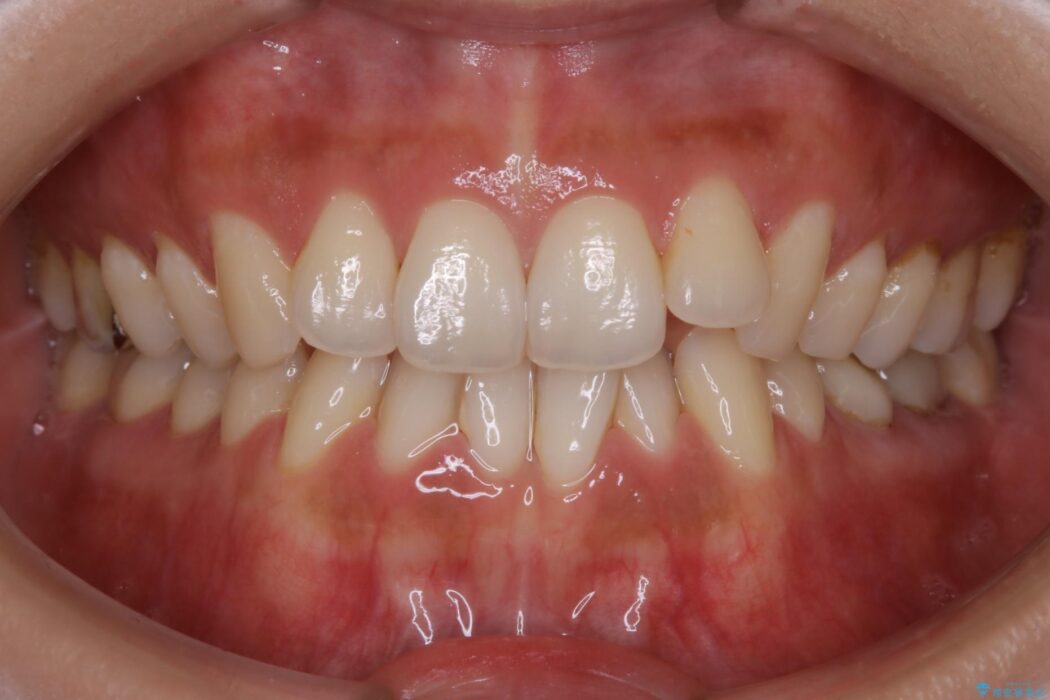

治療後について

笑った時の歯の見え方が改善され患者様にご満足いただけました。